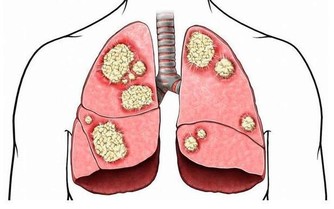

抗生素又是一把雙刃劍,它能夠有效控制感染,但是過度使用甚至濫用,“聰明”的細菌會發生變異甚至耐藥,最後可能一個小小的感冒也會置人於死地,所以我們不能再自以為的濫用消炎藥了,因為一個不經意的習慣帶給您的或許是一個巨大的傷害。

濫用抗生素使越來越多的細菌產生了耐藥,一些原來使用過的很有效的抗生素在對同樣的人及同樣的疾病漸漸失去了效力,使用後感染引起的發熱不退,感染灶也不見縮小或消退。為此,專家們不得不絞盡腦汁,去研究發現對付耐藥菌的新型抗生素。讓人煩惱的是,新抗生素的發現速度遠遠還趕不上細菌產生耐藥的速度,而且耐藥細菌的毒力變得越來越強,越來越難以處置。為了對付細菌的耐藥性,醫生們不得不同時使用多種抗生素,聯合使用對付一個病人正面臨的複雜的感染,當然在殺死有害細菌的同時,一些脆弱的益生菌也會同時被“殺死”,導致機體菌群紊亂,降低機體的抵抗力。

還有,抗生素在治療疾病的同時,或多或少帶有各種副作用,如果對它們的副作用不了解而濫用的話,後果將不堪設想。比如有的抗生素會影響聽力,甚至發生耳聾;有的抗生素對腎臟有損害;有的抗生素會引起過敏,使用前一定要做皮試,還有些抗生素使用後飲酒,會出現雙硫崙樣反應等等,因而在選擇時記得千萬要慎重。